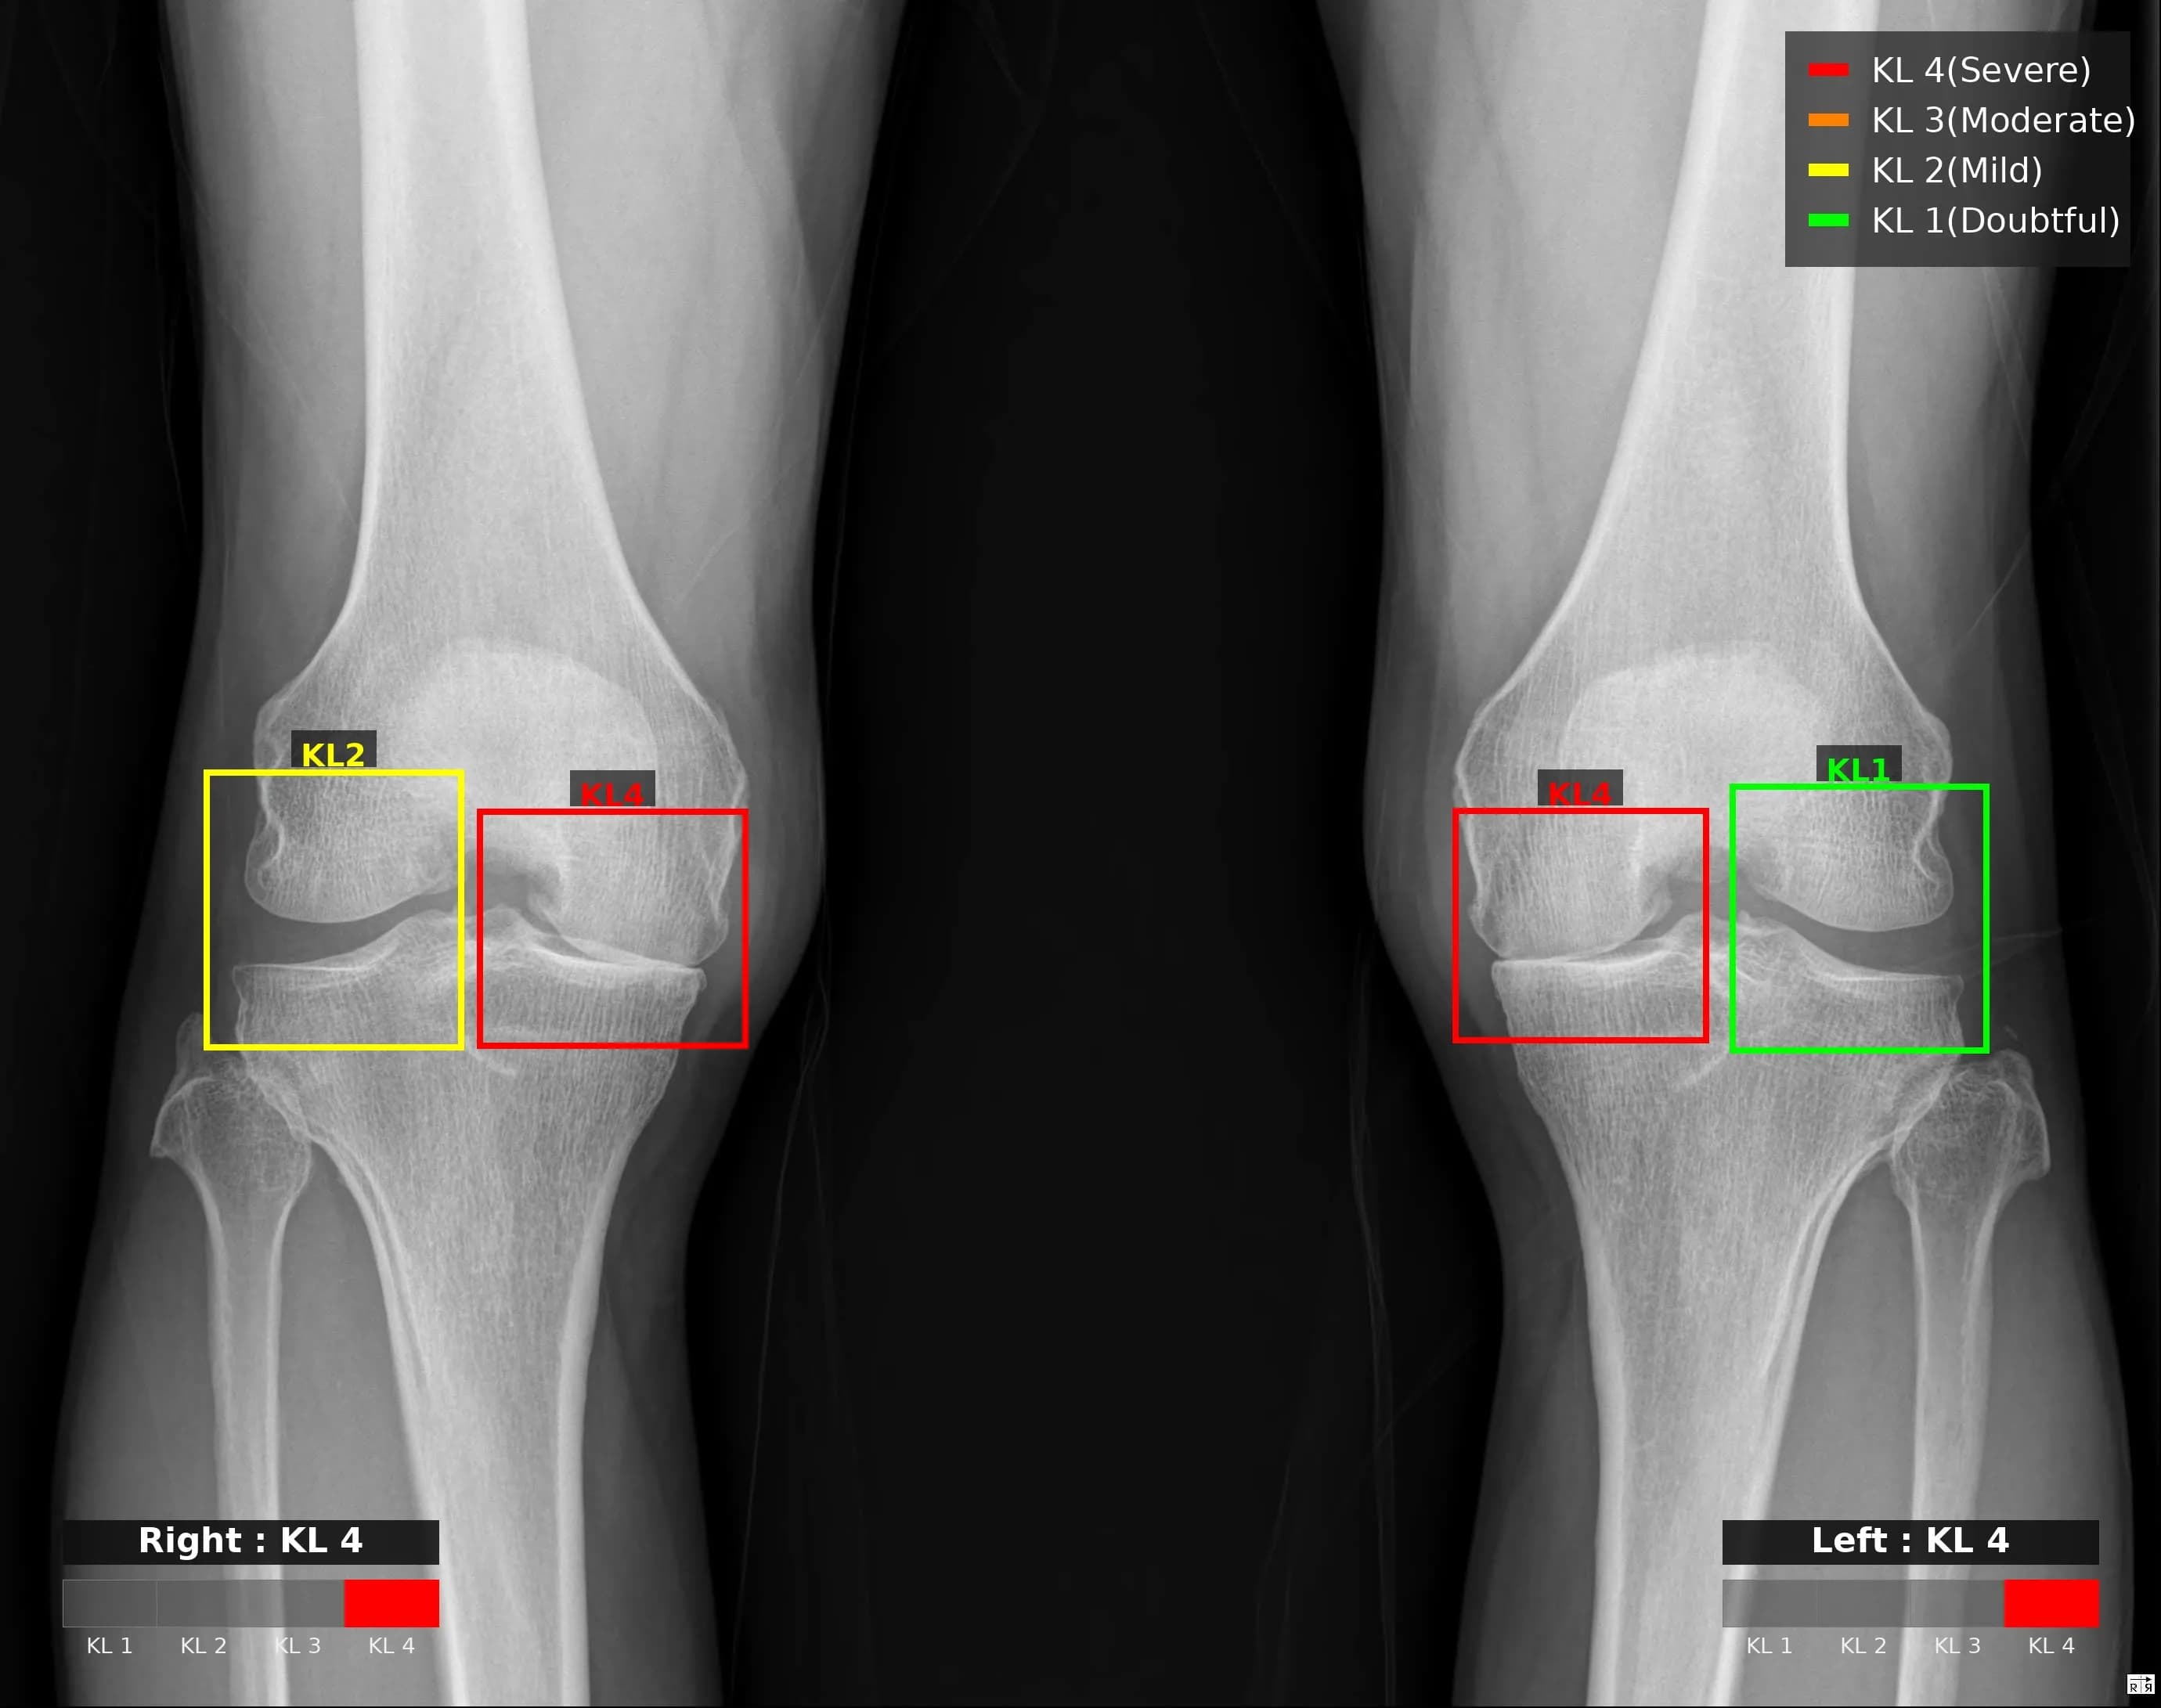

Musculoskeletal X-ray AI Analysis

부위를 클릭하여 결과 이미지를 확인하실 수 있습니다.